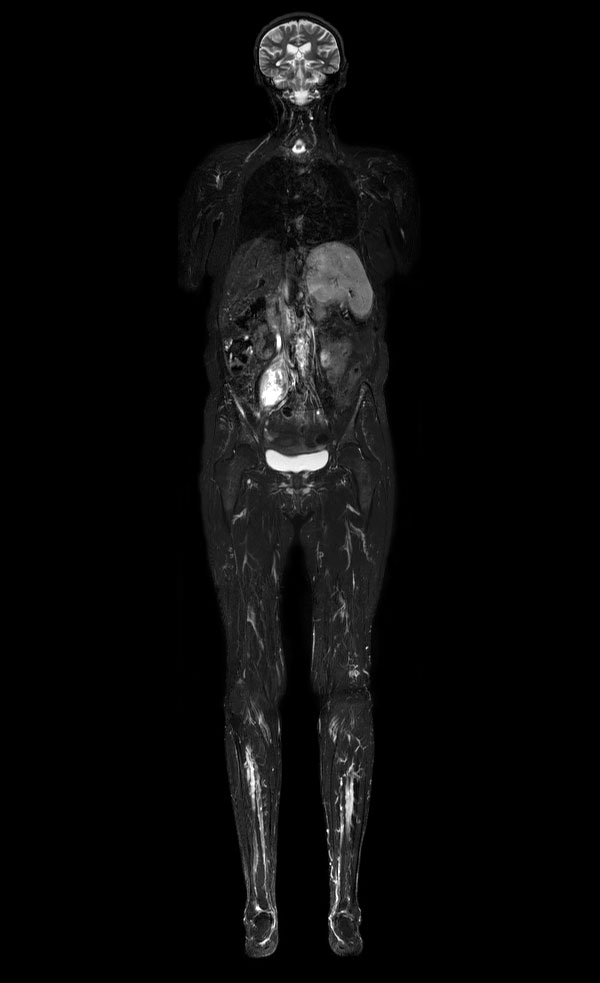

Axial DWIBS (MIP)